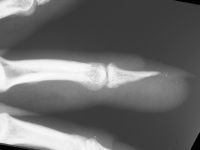

| Case

4. A dog bit off this young man's index fingertip. Although the PA Xray looks as though the bone was kept, additional views show an amputation through the tuft. |